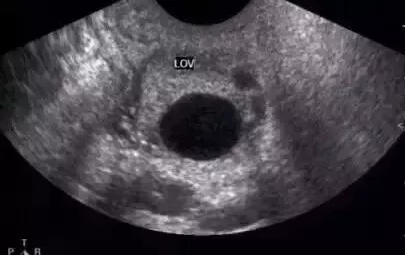

正常成熟的優勢卵泡的聲像圖

① 卵泡最大直徑達20mm,優勢卵泡最大直徑范圍為17~24mm,體積2.5~8.5mm³。徑小于17mm者為非成熟卵泡。

② 卵泡外形飽滿呈圓形或橢圓形,內壁薄而清晰,或可見內壁卵丘所形成的一金字塔形的高回聲,多在排卵前24~30小時易于顯示。亦可見優勢卵泡周圍有一低回聲暈(多由排卵前卵泡膜組織水腫所致)。

③ 卵泡位置移向卵巢表面,且一側無卵巢組織覆蓋,并向外突出。

卵泡的聲像表現為圓形或橢圓形無回聲區,位于卵巢皮質內,邊界清晰,囊壁菲薄,內壁光滑。在月經的早期,卵巢皮質內可見多個直徑3~5mm的小卵泡,隨著月經周期的推移,卵泡逐漸增大,形成優勢卵泡,而其它小卵泡逐漸萎縮。主導卵泡成熟,逐漸突出于卵巢表面。對卵泡的觀察除注意其形態、數目、回聲外,測量卵泡的大小對了解其生長發育狀態、藥物治療效果以及判斷卵泡成熟是十分重要的。

① 卵泡最大直徑超過20mm,排卵前正常卵泡最大直徑范圍為17~24mm。

② 卵泡外形飽滿呈圓形或橢圓形,內壁薄而清晰。

③ 卵泡位置移向卵巢表面,且一側無卵巢組織覆蓋,并向外突出。如果在測卵泡的時候出現卵丘,即意味著即將排卵(卵丘的出現率卵泡內一側內壁上可見細小高回聲點,即為卵丘)。